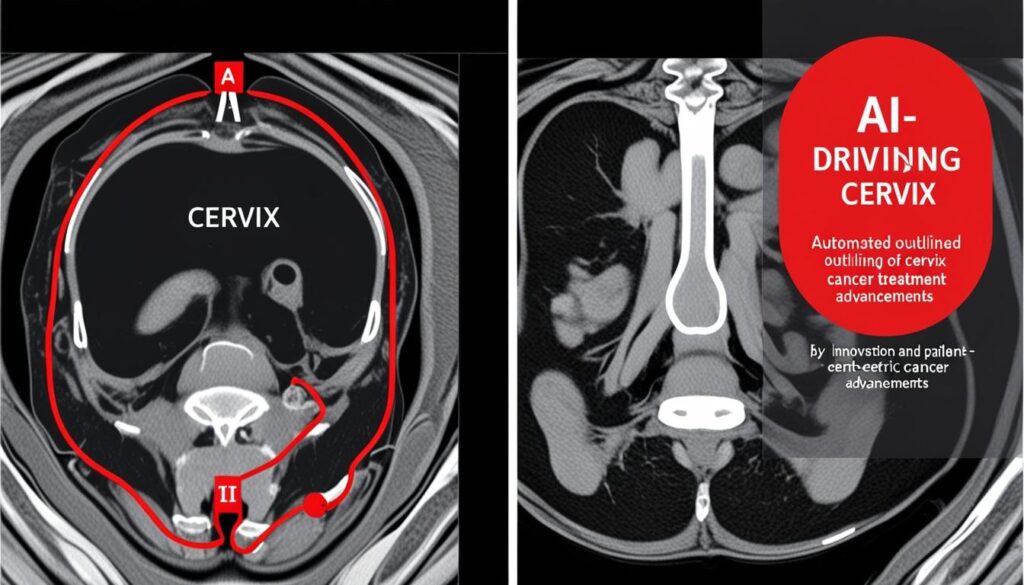

The newly launched tool has been successfully trialled at The Clatterbridge Cancer Centre and several other hospitals. It operates by detecting and automatically outlining essential organs within MRI scans, streamlining the treatment planning process. Automation X believes that this tool could revolutionize the workflow in brachytherapy.

The standard procedure for brachytherapy begins with the insertion of an applicator during a theatre session under general anaesthesia. Post-recovery, patients undergo an MRI scan, which generates detailed, slice-by-slice images of the cancer and surrounding vital organs, facilitating the formulation of a precise treatment plan. The actual radiation treatment is then administered through the applicator, which is subsequently removed.